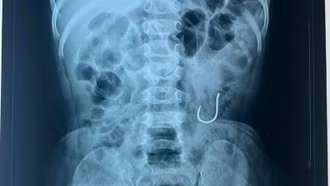

Đẩy thành công dị vật lưỡi câu ra khỏi cơ thể bệnh nhi 16 tháng tuổi

Sau 3 ngày điều trị, chiếc lưỡi câu đã được đẩy thành công ra khỏi cơ thể bệnh nhi 16 tháng tuổi.